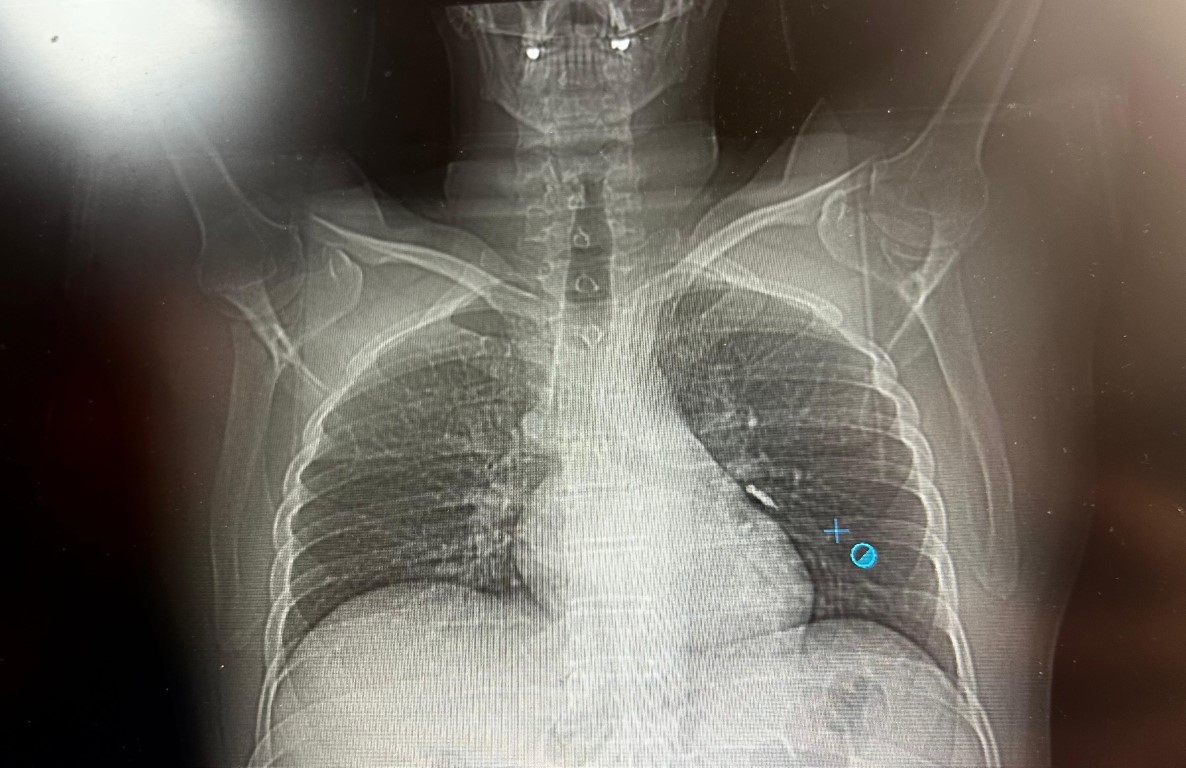

Konuya ilişkin konuşan Göğüs Cerrahi Op. Dr. Sadullah Aksoy, bir diş merkezinde diş tedavisi sırasında hastanın çenesine yerleştirilen implantın vida kısmının işlem esnasında yanlışlıkla aspire edildiğini belirtti. İlk olarak hastanenin ek hizmet binasında çekilen tomografi sonucunda, vidanın sol akciğerin hava yollarının yaklaşık dördüncü dalına kadar ilerlediği tespit edildiğini ifade eden Op. Dr. Aksoy, "Geçtiğimiz cumartesi günü öğle saatlerinde tarafımıza ulaşıldığında, hastanın Van Eğitim ve Araştırma Hastanesi’ne yönlendirilmesini istedik. Burada acil bronkoskopi planı yapılarak hasta kabul edildi. Hasta geldiğinde genel durumu iyiydi; solunumunu tamamen engelleyen bir bronş tıkanıklığı söz konusu değildi. Aynı gün hastamızı hazırladık. Bronkoskopi sırasında, implant vidasının sol üst lobun anterior segment bronşuna saplanmış pozisyonda olduğunu gördük. Üroloji bölümünde taş çıkarma işlemlerinde kullanılan cihazla müdahale ettik. İlk denemede implant tamamen çıkarılamadı ancak yerinden oynatılabildi. Bunun üzerine bir süre bekleyip hastayı yeniden bronkoskopi için hazırlamaya başladık. İşlem yaklaşık 3,5-4 saat sürdü ve saat 18.30 civarında hasta işlemden çıkarıldı" dedi.

Daha sonra hasta için yeniden bronkoskopi planladıklarını ancak bu süreçte hasta şiddetli bir öksürük geçirdiğini anlatan Aksoy, "Şiddetli öksürük sonrası yapılan kontrol akciğer filminde implant vidası görünmedi. Bunun üzerine toraks ve batın BT (bilgisayarlı tomografi) görüntülemesi istedik. Sonuçlarda implantın akciğerden çıktığı ve vücutta herhangi bir yerde bulunmadığı tespit edildi" diye konuştu.